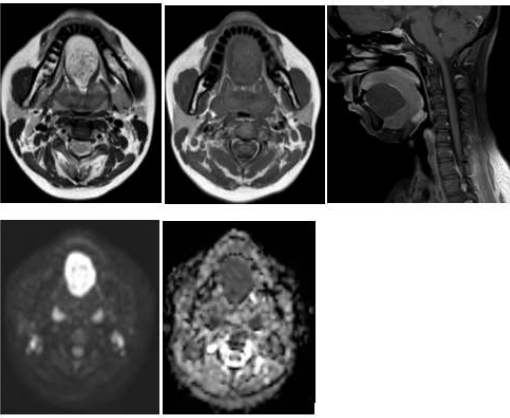

A 29-year-old woman reported a gradually increasing swelling beneath the tongue that had been present for approximately seven months. She had no pain, infection, or systemic symptoms, and the overlying mucosa appeared normal. On palpation the lesion was soft, dough like and non-tender. The mass elevated the tongue slightly, leading to mild difficulty with speech and swallowing. No abnormal lymph nodes were detected. Patient underwent magnetic resonance imaging of the neck and oral cavity which revealed a well-circumscribed cystic lesion in the sublingual region in midline above the mylohyoid muscle. The mass showed low signal on T1-weighted images, high signal on T2-weighted sequences, with minimal peripheral enhancement on post contrast images. There was significant diffusion restriction on DW/ADC images [ figure 1]. These findings were consistent with epidermoid cyst as keratin-filled cyst causes restriction of movement of water molecules. The lesion was removed surgically using an intraoral approach. Recovery was smooth, and the patient experienced no complications. Histopathologic evaluation revealed a cyst lined by keratinizing squamous epithelium with laminated keratin in the lumen, confirming the diagnosis of an epidermoid cyst.

Figure 1: A midline swelling is seen in the floor of the mouth (A – E): A. Cyst appearing hyperintense on T2W images B. Hypointense on T1W images C. displays minimal peripheral enhancement on post contrast images and D& E. restricted diffusion on DW and ADC images confirming the diagnosis of epidermoid cyst.